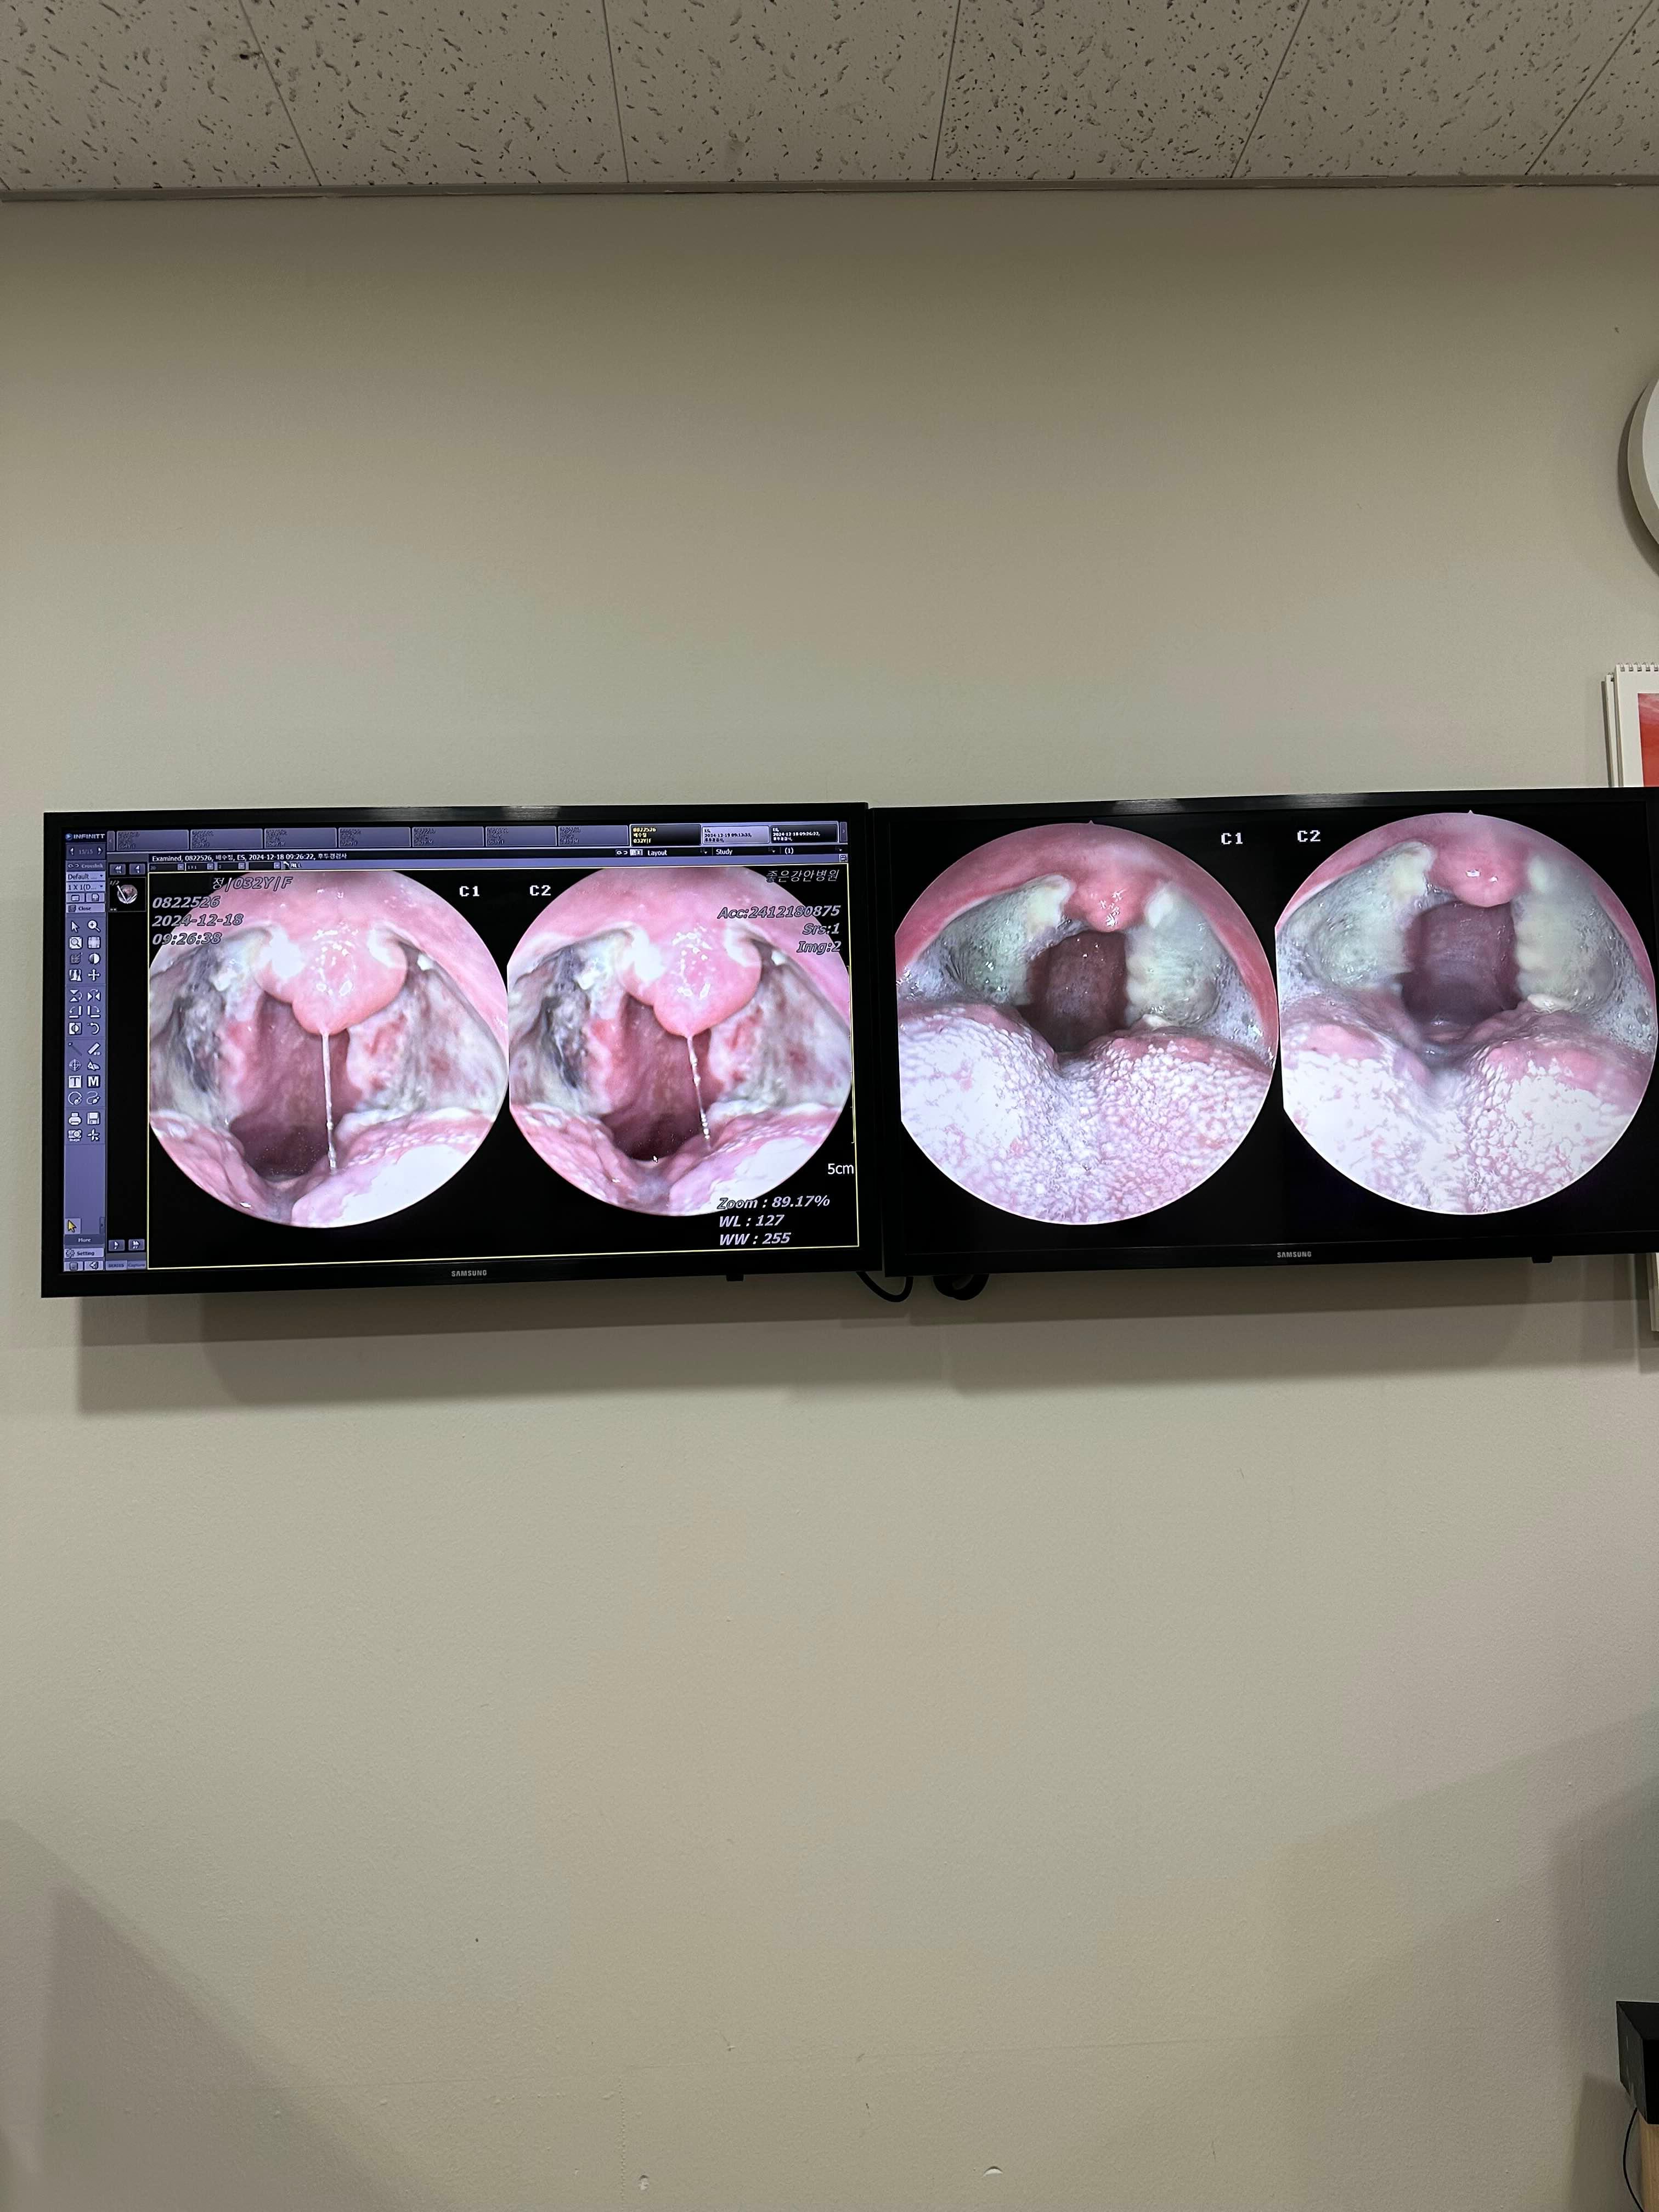

수술후

왼) 수술 이틀뒤

오) 수술 후 7일경과

나는 이때가 젤아팠음..

새벽에 기침을 자꾸해서 ㅜㅜ 아침에 넘힘듬

혀를 닦아도 백태처럼 남아있고..

이때 약 1주일분 더 받아서 꼬박꼬박 잘먹음.